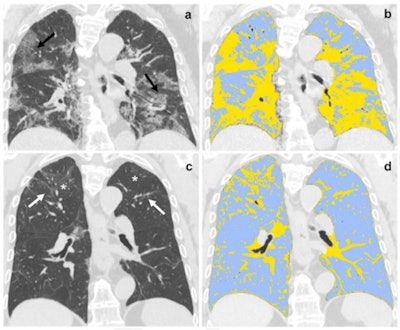

"[Our study found that] at six-month follow-up, 72% of patients showed late sequelae, in particular fibrotic-like changes," the team wrote. "Baseline LSS [Lung Severity Score] and QCCT [quantitative chest CT] of well-aerated lung showed an excellent performance in predicting [these] changes at six-month chest CT."

At six-month chest CT follow-up, 72% of patients had fibrotic-like changes in their lungs and 42% showed ground-glass opacities. The investigators found that baseline LSS and QCCT scores were effective predictors of fibrotic-like changes at this follow-up exam.